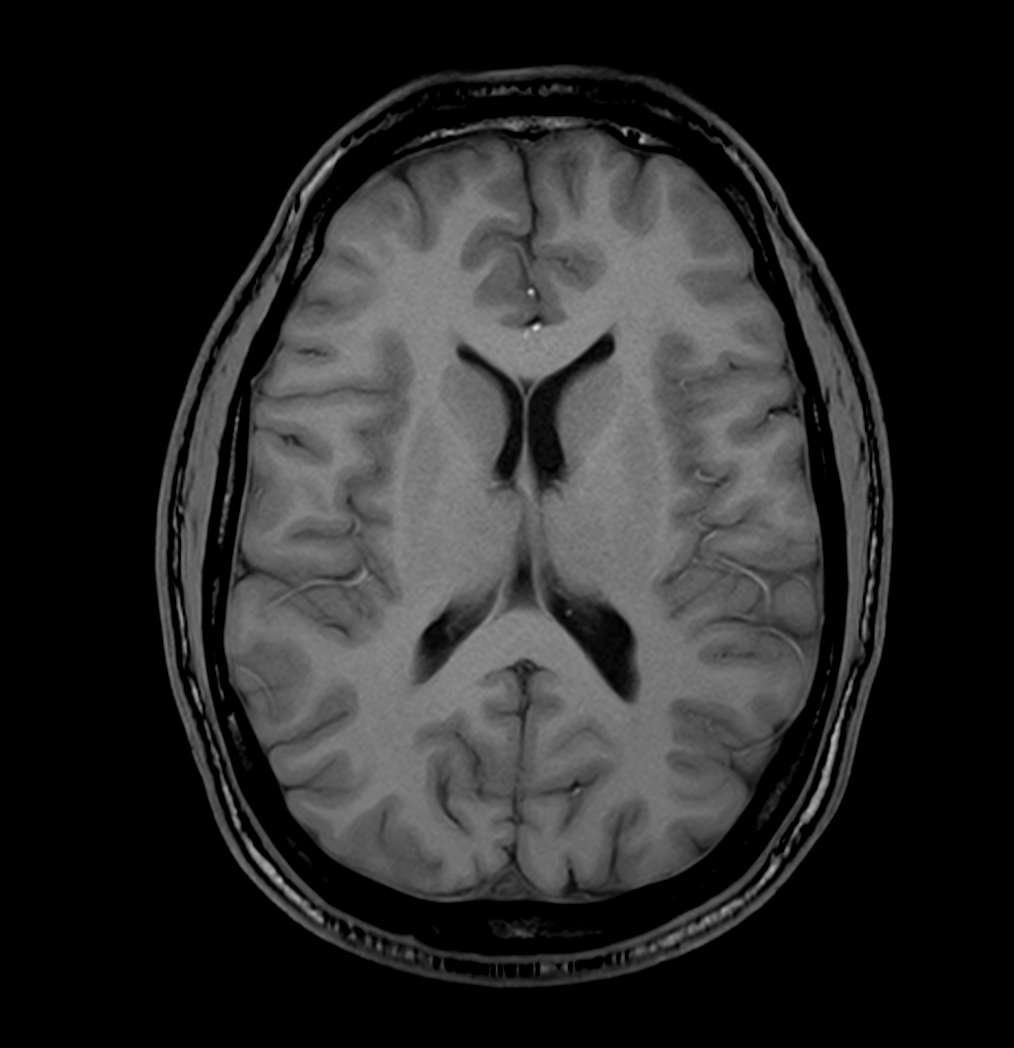

T1w 3D FFE (axial reformat)